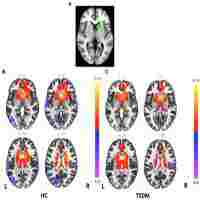

| Description | Journal: Human brain mapping The critical roles of frontostriatal circuits had been revealed in addiction. With regard to young smokers, the implication of frontostriatal circuits resting-state functional connectivity (RSFC) in smoking behaviors and cognitive control deficits remains unclear. In this study, the volume of striatum subsets, i.e., caudate, putamen, and nucleus accumbens, and corresponding RSFC differences were investigated between young smokers (n1 = 60) and nonsmokers (n2 = 60), which were then correlated with cigarette smoking measures, such as pack_years-cumulative effect of smoking, Fagerström Test for Nicotine Dependence (FTND)-severity of nicotine addiction, Questionnaire on Smoking Urges (QSU)-craving state, and Stroop task performances. Additionally, mediation analysis was carried out to test whether the frontostriatal RSFC mediates the relationship between striatum morphometry and cognitive control behaviors in young smokers when applicable. We revealed increased volume of right caudate and reduced RSFC between caudate and dorsolateral prefrontal cortex (DLPFC), orbitofrontal cortex in young smokers. Significant positive correlation between right caudate volume and QSU as well as negative correlation between anterior cingulate cortex-right caudate RSFC and FTND were detected in young smokers. More importantly, DLPFC-caudate RSFC strength mediated the relationship between caudate volume and incongruent errors during Stroop task in young smokers. Our results demonstrated that young smokers showed abnormal interactions within frontostriatal circuits, which were associated with smoking behaviors and cognitive control impairments. It is hoped that our study focusing on frontostriatal circuits could provide new insights into the neural correlates and potential novel therapeutic targets for treatment of young smokers. Hum Brain Mapp 37:2013-2026, 2016. © 2016 Wiley Periodicals, Inc. |